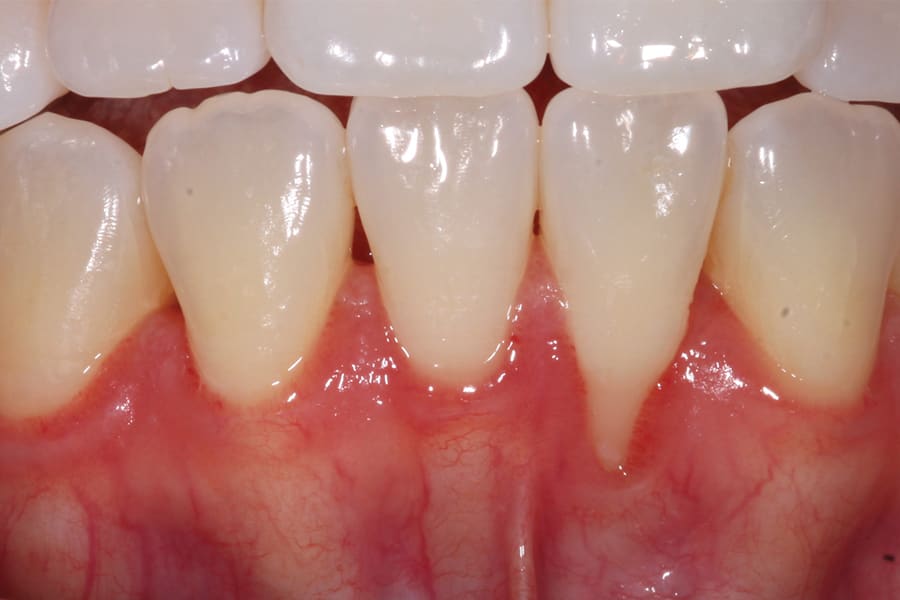

There are, however, some unfavorable long-term ramifications of this design. Due to the nature of stainless steel, which has memory and over time will partially return to its original shape, these twisted lingual retainers may "unwind" or uncoil and exert unintended forces on the teeth to which they are bonded (Figure 5 and Figure 6, Figure 8 through Figure 11, Figure 14 through Figure 16). This leads to excessive labial or lingual root torquing movements, often resulting in highly undesirable recessions, dehiscences, and fenestrations. Because it may take years for this occurrence to manifest, the orthodontist (who usually places the retainer) is typically both unaware of the situation, as he or she does not customarily follow patients for such long-term periods, and free of blame. The periodontal implications of this outcome can be highly detrimental, as seen in the cases presented herein.

Although spontaneous improvement of the investing tissues is often observed through orthodontic correction (Figure 7 and Figure 13),5 additional corrective action is frequently indicated afterwards, particularly when cosmetics are to be considered. A recession defect case is depicted in Figure 17 through Figure 26 in which corrective action was necessary and accomplished through aligner therapy followed by connective tissue grafting.6 It should be noted that although this corrective scheme may successfully achieve an acceptable cosmetic and functional result, it is not likely a regenerative outcome in the sense that a previously dehisced root surface typically will not attain ligamentous insertion into freshly laid cementum. A long junctional epithelium or connective tissue attachment at best is the more likely outcome. Consequently, a preventive approach initially would be more desirable.